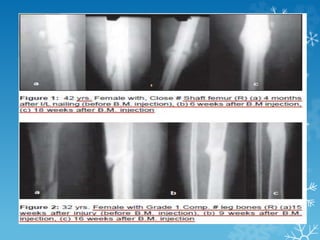

 BOYD Said that “Bone grafting is primarily a second

wounding procedure, in which surgeon hopes that the

response of the body will be more favorable than the

response following the original trauma”.

 The most productive source of cells that influence

osteogenesis is considered to Autlogous bone marrow.

PERCUTANEOUS

AUTOLOGOUS BONE MARROW

INJECTION

 Connolly et al also stated “Autologous bone marrow has

been most useful for the preventive treatment of

nonunion by early injection of delayed union”.

 He also said that the ideal time for bone marrow

injection should be after the initial inflammatory and

osteoclastic resorption period.

 Marrow by itself does not serve as an osteoconductive

agent and therefore cannot fill a large gap,But as

composite graft with demineralized bone matrix, porous

ceramic materials, xenograft .

 The standard procedure

of aspiration of bone

marrow. The procedure

was carried out as an

outpatient procedure.

 Under local infiltration

with 2% xylocaine, a 16-

gauge bone marrow

aspiration needle was

used and to inject the

marrow at fracture site

with needle of 16-gauge

in cases of tibia or ulna.

 Image intensifier was

used to locate the area of

bone marrow injection.

 The volume of bone marrow injected was between 50-90

ml in cases of tibia and femur. In ulna the amount

injected was 15 ml only.

 Autologous marrow grafting is a simple and effective

method of providing cellular reactivation of osteogenesis

without the complications and risks of cancellous bone

grafting.

 The method can be used as an early intervention,

whenever one suspects a delay in the healing of

fracture.

 This procedure can be done on an outpatient basis and

even under local anesthesia